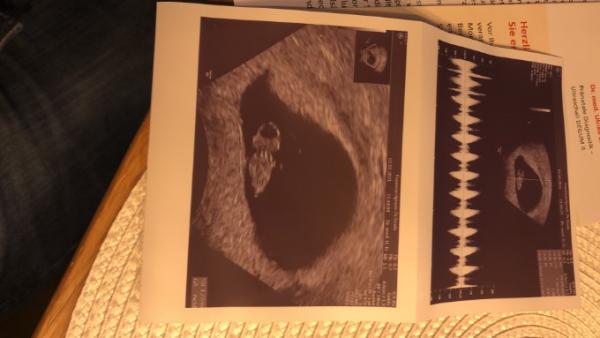

Ich war Dienstag beim Frauenarzt es war alles super und das Herz hat geschlagen

7+3 war es